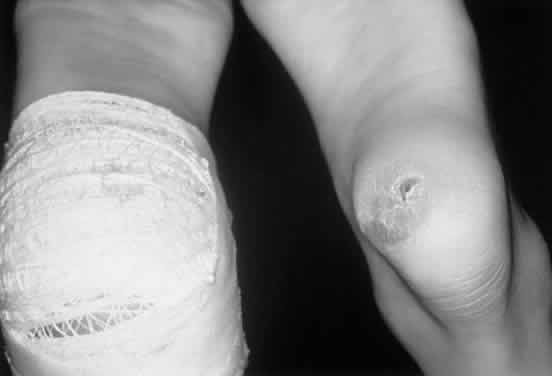

HUNTER SYNDROME (MPS II)

There are mild (type B) and severe (type A) forms of Hunter syndrome. They are distinguished on clinical grounds only and have a wide spectrum of clinical severity. The two types are allelic and are caused by mutations at the X-linked locus for the enzyme iduronate sulfate sulfatase. Wilson et al27 localized the gene to Xq28, distal to the fragile X site. Characteristic pebbly, ivory-colored skin lesions over the back, neck, scapula, and thigh are present in patients with MPS II (Fig. 4).

Fig. 4. Nodular skin lesions in the scapular area of a patient with Hunter syndrome.